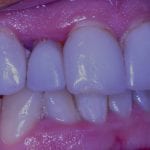

Post op intra-oral scan with Medit i500 to capture irritated and hemorrhaging tissue (for demonstration purposes only)